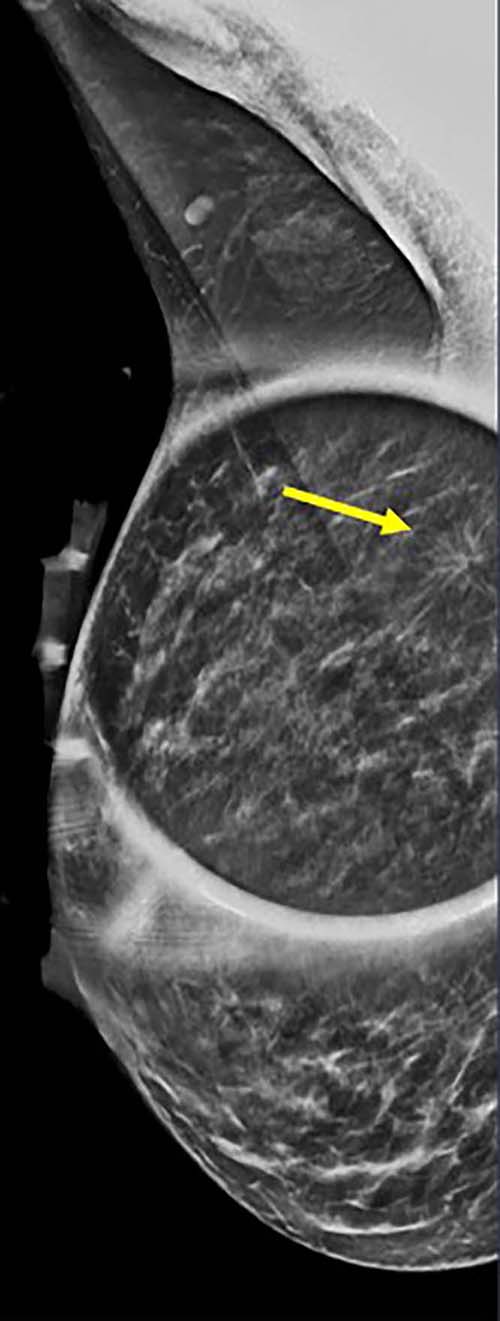

Figure 1. 40-year-old patient presents for routine screening. Family history of paternal grandmother age 55. Extremely dense breast tissue is noted on mammography right and left craniocaudal (taken from the top of the breast) view.

Figure 3. Spot on right mediolateral oblique (side angle) view. Area of distortion persists on additional mammographic views, and a mass is identified on subsequent breast ultrasound. Ultrasound guided biopsy was performed and revealed nuclear grade 1 invasive ductal carcinoma.